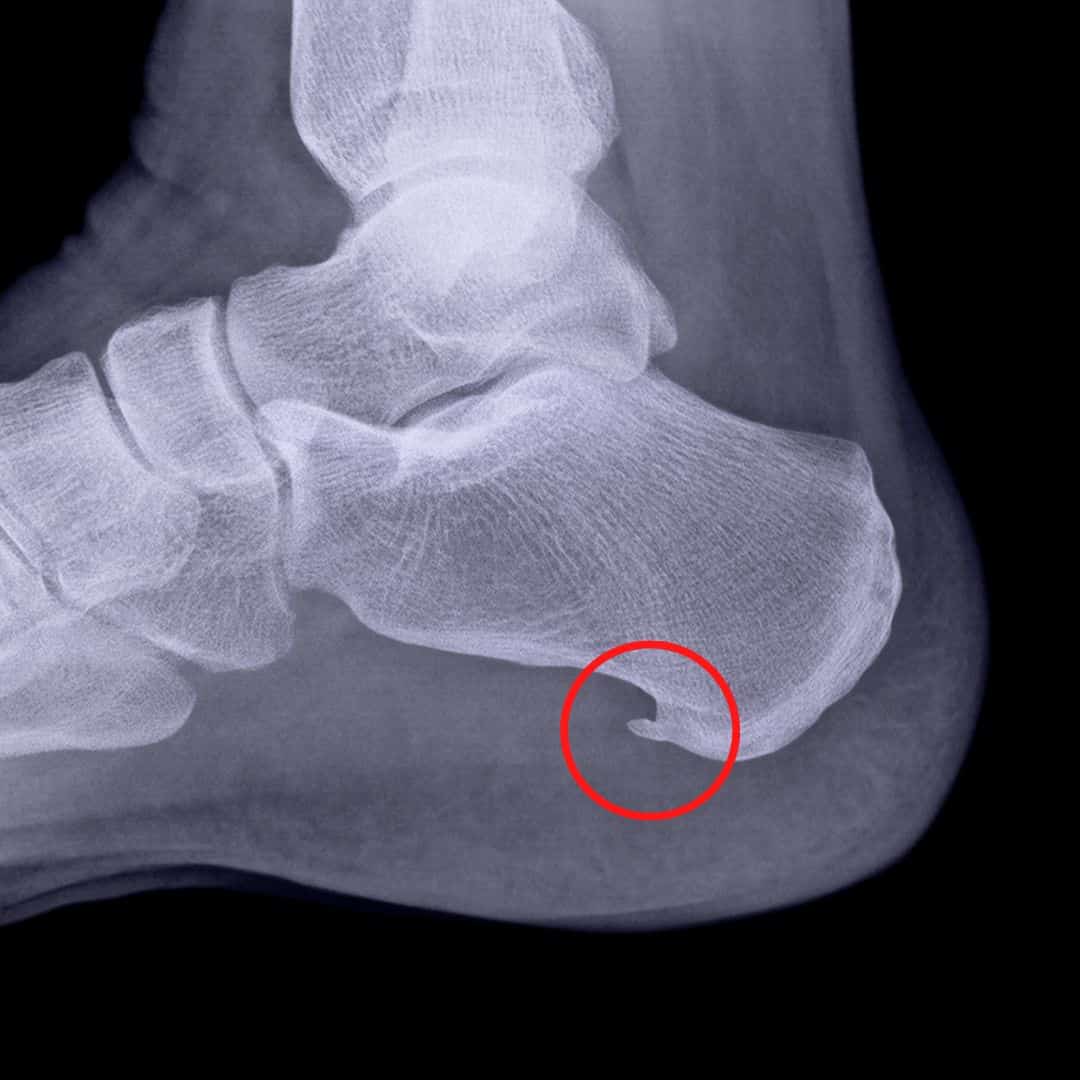

Patní ostruha není žádný zákeřný útvar, který se do těla vetře zvenku. Je to reakce těla na přetížení → konkrétně na dlouhodobé napětí šlachy, která se upíná na patní kost.

Tělo je moudré a za každou cenu se snaží pomoci. Říka: „Aha, tady je velké tahání, tak udělám to místo pevnější.“ A vytvoří kostní výrůstek, který má chránit. Jenže místo pomoci vzniká problém – bolest. Nejvíc bolí při prvním kroku ráno nebo po delším sezení. Jakmile se „rozejdeš“, bývá to lepší… ale to neznamená, že je po problému.

Pod patou máme úžasnou strukturu zvanou plantární fascie – pružný „popruh“, který drží tvar nožní klenby a pomáhá tlumit nárazy při chůzi. Když ji dlouhodobě přetěžujeme (špatná obuv, tvrdé povrchy, oslabené svaly chodidel), fascie se začne bránit. Mikroskopické trhlinky → zánět → a tělo, v dobré víře, začne místo hojit kostí. Takhle vzniká patní ostruha.